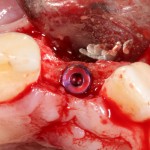

Другой вариант. Имплантируем, но существующего объема костной ткани недостаточно для получения адекватного эстетического и функционального результата:

Поэтому мы используем мембрану Geistlich BioGide и всё ту же аутокостную стружку: